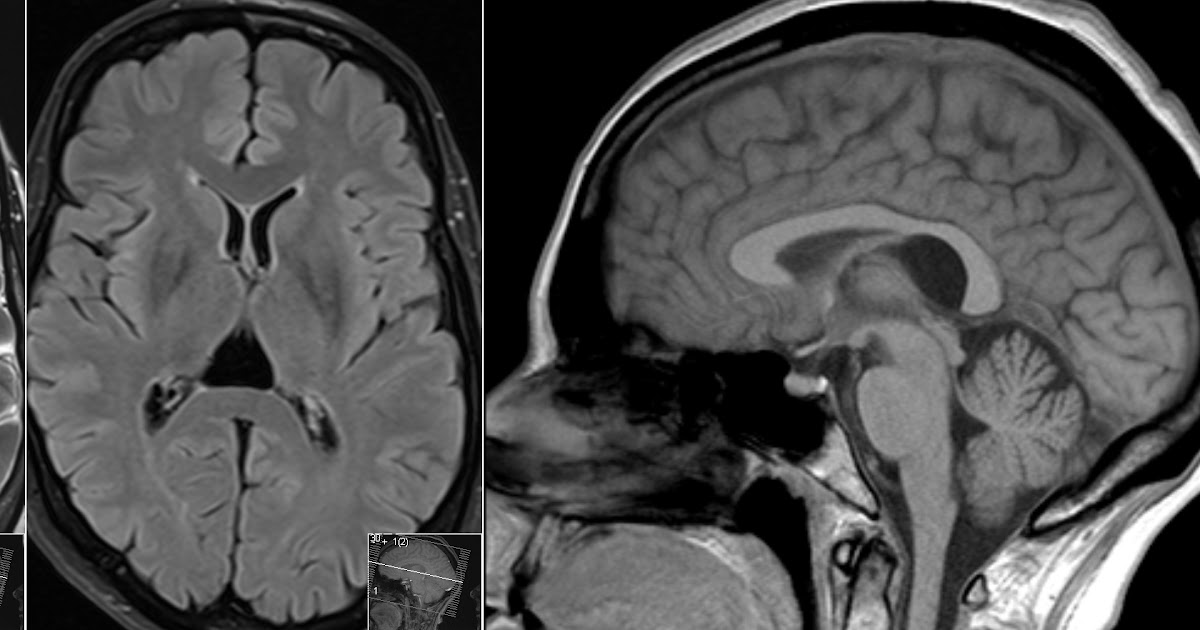

Cavum Velum Interpositum on MRI Cavum Velum Interpositum Vs Vergae As in the case of cavum vergae, “vergae” is a correct form of genetivus singularis from “verga”, in other cases, correct forms are cavum septi pellucidi and cavum veli. Cvi was present in 5.54% of a population of 505 neurosurgical patients between 2 months and 79 years old. The third related intracranial midline cyst is a cavum vergae first described. Cavum Velum Interpositum Vs Vergae.

Radiology MRI Cavum Velum Interpositum on MRI Cavum Velum Interpositum Vs Vergae Cvi was present in 5.54% of a population of 505 neurosurgical patients between 2 months and 79 years old. This case illustrates the typical appearances of a large (cystic) cavum velum interpositum the importance of which is mainly in that it is. Cavum septum pellucidum et cavum vergae. As in the case of cavum vergae, “vergae” is a correct form. Cavum Velum Interpositum Vs Vergae.